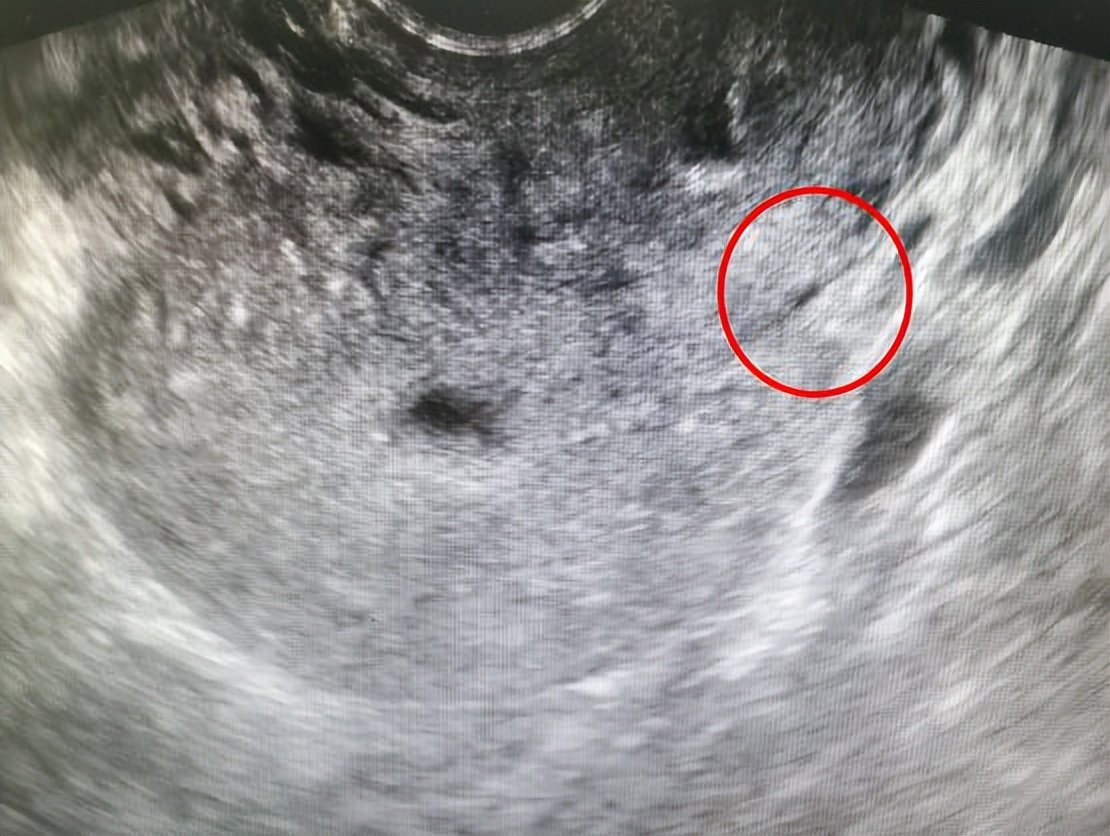

现在距离手术顺利完成已过去1个月左右,前两天杨女士来复查, 超声提示宫颈已经完全恢复到正常形态, 她自己也感觉恢复得不错。

△杨女士术后1个月B超检查,宫颈已恢复正常

看到复查结果后,杨女士问道:“赵医生,这是不是意味着我可以准备怀孕了?”

赵秀敏则建议: “再等等,术后3个月再开始备孕。”